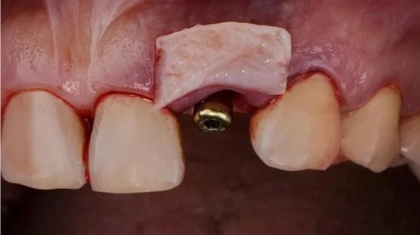

- เพื่อเตรียมพื้นที่สำหรับทันตกรรมอื่นๆ เช่น การทำรากฟันเทียม หรือการจัดฟัน ที่ต้องการฐานเหงือกที่แข็งแรงและมีปริมาณเพียงพอ

วิธีการปลูกเหงือกแบบต่างๆ

3. การปลูกถ่ายเหงือกแบบเลื่อนแผ่นเหงือก (Pedicle Graft)

การปลูกถ่ายเหงือกแบบเลื่อนแผ่นเหงือกเป็นวิธีการรักษาทางทันตกรรมที่ใช้แก้ไขปัญหาเหงือกร่น โดยไม่จำเป็นต้องตัดชิ้นเนื้อเยื่อจากบริเวณเพดานปาก แต่ใช้วิธีการเลื่อนเนื้อเยื่อจากบริเวณใกล้เคียงมาปิดส่วนที่มีปัญหาแทน

ขั้นตอนการทำ:

- ทันตแพทย์ประเมินบริเวณที่ต้องการรักษาและเนื้อเยื่อข้างเคียง

- ทำการกรีดเหงือกบริเวณด้านข้างหรือเหนือฟันที่มีปัญหา

- เลื่อนแผ่นเหงือกที่กรีดไว้มาปิดบริเวณรากฟันที่เผยออกมา โดยยังคงให้ส่วนฐานของเนื้อเยื่อติดอยู่กับตำแหน่งเดิม

- เย็บแผ่นเหงือกให้อยู่ในตำแหน่งใหม่

- ดูแลแผลผ่าตัดและติดตามผลการรักษา